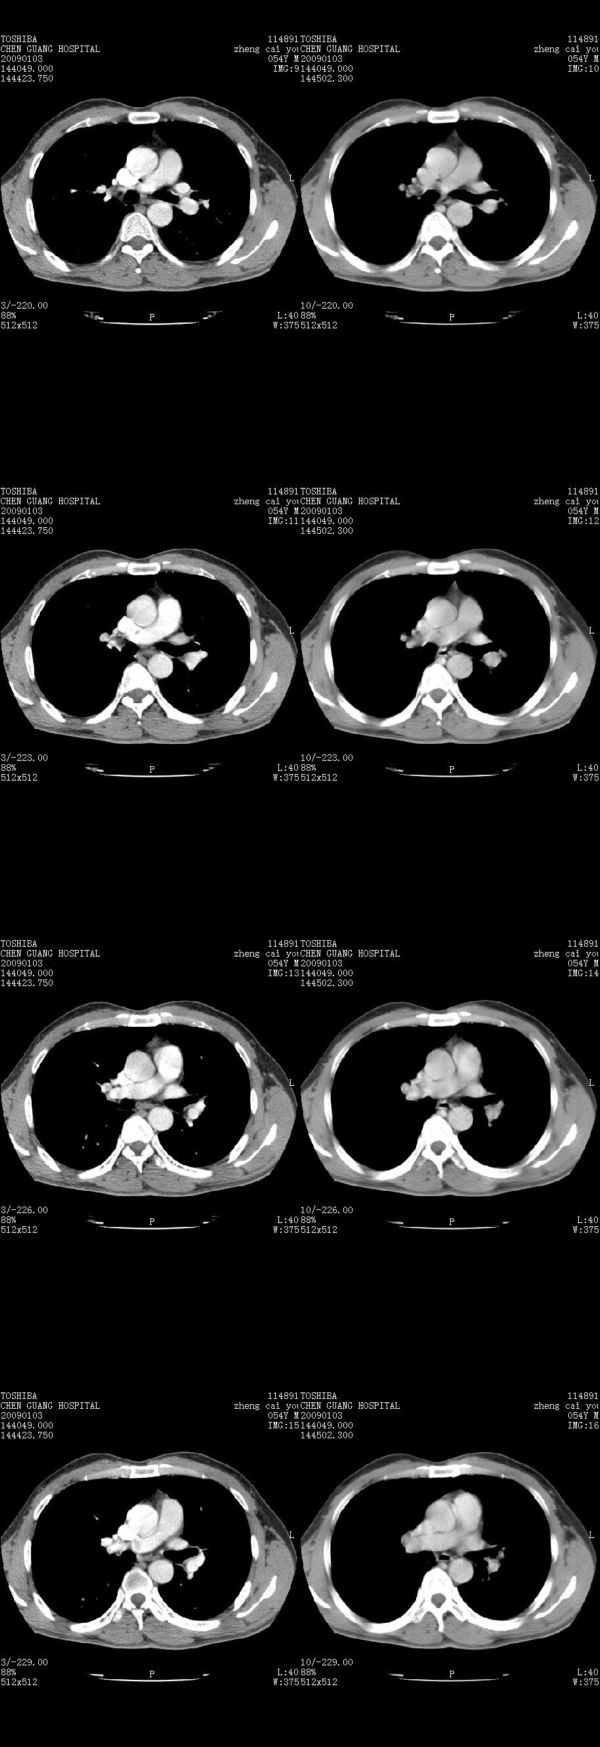

男,54岁,右侧胸部疼痛,平时吸烟,有抽烟后咳嗽咯痰史。昨天没把xiphoid软件吃懂,所以没把纵隔窗图像处理出来!请各位老师帮忙看一下右肺门有没有问题?谢谢!!!!!!!!!!

右肺上叶后段近气管旁仍可见一结节灶,不除外为肿大的淋巴结影。

气管前腔静脉后似见增大淋巴结影,肺门区未见明显肿块影。肺窗示右肺中叶外侧段透亮度增高,可过一段时间再查一下对比一下,毕竟是自己的至亲,又有条件,辐射就顾不得了。

也觉得还好吧,只是右下肺动脉显粗了点,纵膈有钙化淋巴结,再有肺窗就更好了

各位老师:奇静脉增宽,肺上未见明显实变,这还需注意观察些什么?????

上腔静脉后淋巴结影,不知道最后结果怎么样?